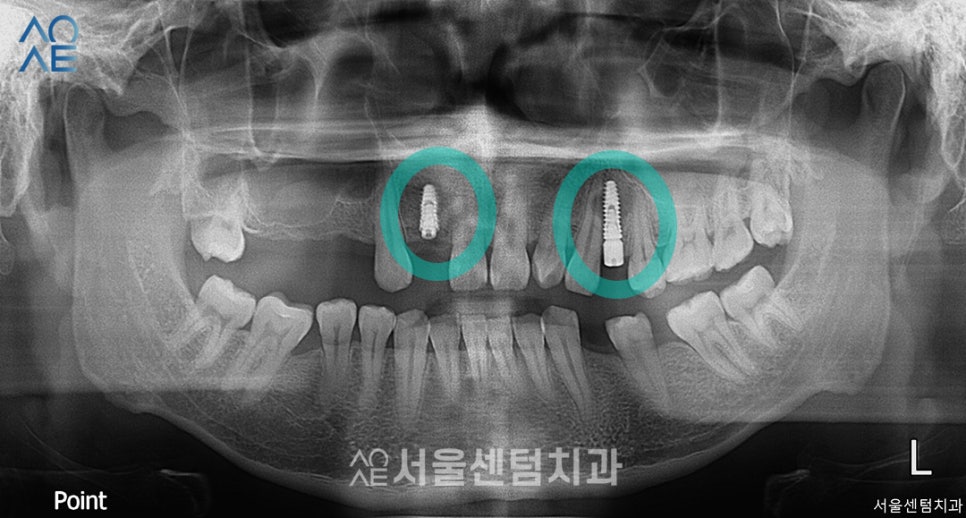

위에서 말씀드린 것처럼

상담 당일에 바로 수술을 진행했습니다.

또 잇몸뼈가 부족하다고 진단했기 때문에

뼈이식도 함께 진행했습니다.

이날은 2개만 먼저 진행했으며

충분히 잇몸뼈가 형성되는 기간이 필요하기에

5주 뒤 ct촬영 후 2차수술을 진행하기로 했습니다.

약 한달 뒤 촬영한 모습입니다.

다행히 잇몸뼈가 잘 형성되고 있는 모습입니다.

지난번 식립한 부분을 확인하면서

위-오른쪽 어금니에도 3개 추가 식립하였습니다.

역시나 뼈이식도 함께 진행하였습니다.